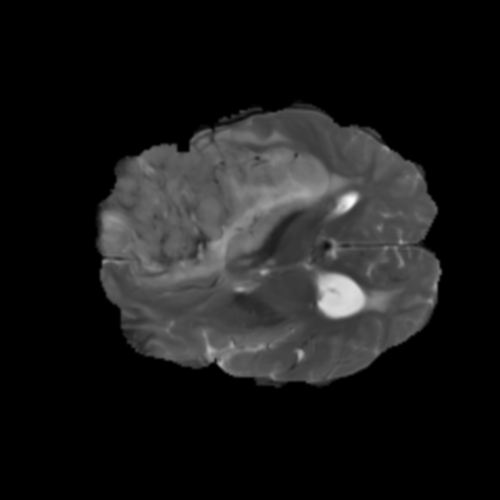

Ejemplos de Modalidades MRI

Visualización de las 4 modalidades de resonancia magnética y las segmentaciones de zonas tumorales utilizadas para entrenar el modelo

Glioma de Alto Grado (HGG)

FLAIR HGG

FLAIR

T1ce HGG

T1ce

T2 HGG

T2

T1 HGG

T1

📊 Modalidades de MRI Utilizadas

• T1: Secuencia ponderada en T1, proporciona gran detalle anatómico con líquidos oscuros

• T1ce: T1 con realce de contraste (Gadolinio), ilumina partes activas del tumor con barrera hematoencefálica comprometida

• T2: Secuencia ponderada en T2, sensible a patologías donde líquidos aparecen brillantes

• FLAIR: Recuperación de inversión atenuada en fluidos, similar a T2 pero suprime señal de LCR para visualizar edema peritumoral